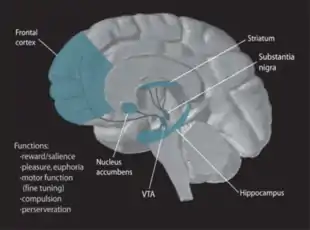

The dorsolateral striatum is associated with the acquisition of habits and is the main neuronal cell nucleus linked to procedural memory. Connecting excitatory afferent nerve fibers help in the regulation of activity in the basal ganglia circuit. Essentially, two parallel information processing pathways diverge from the striatum. Both acting in opposition to each other in the control of movement, they allow for association with other needed functional structures[48] One pathway is direct while the other is indirect and all pathways work together to allow for a functional neural feedback loop. Many looping circuits connect back at the striatum from other areas of the brain; including those from the emotion-center linked limbic cortex, the reward-center linked ventral striatum and other important motor regions related to movement.[49] The main looping circuit involved in the motor skill part of procedural memory is usually called the cortex-basal ganglia-thalamus-cortex loop.[50]

The striatum is unique because it lacks the glutamate-related neurons found throughout most of the brain. Instead, it is categorized by a high concentration of a special type of GABA related inhibiting cell known as the medium spiny neuron.[51] The two parallel pathways previously mentioned travel to and from the striatum and are made up of these same special medium spiny neurons. These neurons are all sensitive to different neurotransmitters and contain a variety of corresponding receptors including dopamine receptors (DRD1, DRD2), muscarinic receptors (M4) and adenosine receptors (A2A). Separate interneurons are known to communicate with striatal spiny neurons in the presence of the somatic nervous system neurotransmitter acetylcholine.[52]

Current understanding of brain anatomy and physiology suggests that striatal neural plasticity is what allows basal ganglia circuits to communicate between structures and to functionally operate in procedural memory processing.[53]

Dopamine

Dopamine is one of the more known neuromodulators involved in procedural memory. Evidence suggests that it may influence neural plasticity in memory systems by adapting brain processing when the environment is changing and an individual is then forced to make a behavioural choice or series of rapid decisions. It is very important in the process of "adaptive navigation", which serves to help different brain areas respond together during a new situation that has many unknown stimuli and features.[58] Dopamine pathways are dispersed all over the brain and this allows for parallel processing in many structures all at the same time. Currently most research points to the mesocorticolimbic dopamine pathway as the system most related to reward learning and psychological conditioning.[59]